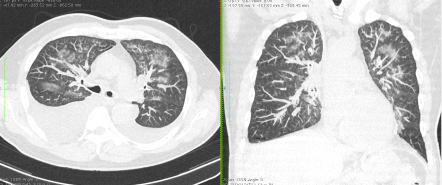

Методы лучевой диагностики применяют для выявления COVID-19 пневмоний, их осложнений, дифференциальной диагностики с другими заболеваниями легких, а также для определения степени выраженности и динамики изменений, оценки эффективности проводимой терапии.

К методам лучевой диагностики патологии ОГК пациентов с предполагаемой/установленной COVID-19 пневмонией относят:

- Компьютерную томографию легких (КТ),

КТ имеет высокую чувствительность в выявлении изменений в легких, характерных для COVID-19. Применение КТ целесообразно для первичной оценки состояния ОГК у пациентов с тяжелыми прогрессирующими формами заболевания, а также для дифференциальной диагностики выявленных изменений и оценки динамики процесса. КТ позволяет выявить характерные изменения в легких у пациентов с COVID-19 еще до появления положительных лабораторных тестов на инфекцию с помощью МАНК. В то же время, КТ выявляет изменения легких у значительного числа пациентов с бессимптомной и легкой формами заболевания, которым не требуется госпитализация. Результаты КТ в этих случаях не влияют на тактику лечения и прогноз заболевания при наличии лабораторного подтверждения COVID-19. Поэтому массовое применение КТ для скрининга асимптомных и легких форм болезни не рекомендуется.

4. Все выявляемые при лучевых исследованиях признаки, включая КТ-симптомы, не являются специфичными для какого-либо вида инфекции и не позволяют установить этиологический диагноз. Вне клинической (эпидемической) ситуации они не позволяют отнести выявленные изменения к пневмонии COVID-19 и дифференцировать их с другими пневмониями и невоспалительными заболеваниями. Данные лучевого исследования не заменяют результаты обследования на РНК SARS-CoV-2. Отсутствие изменений при КТ не исключают наличие COVID-19 и возможность развития пневмонии после проведения исследования.